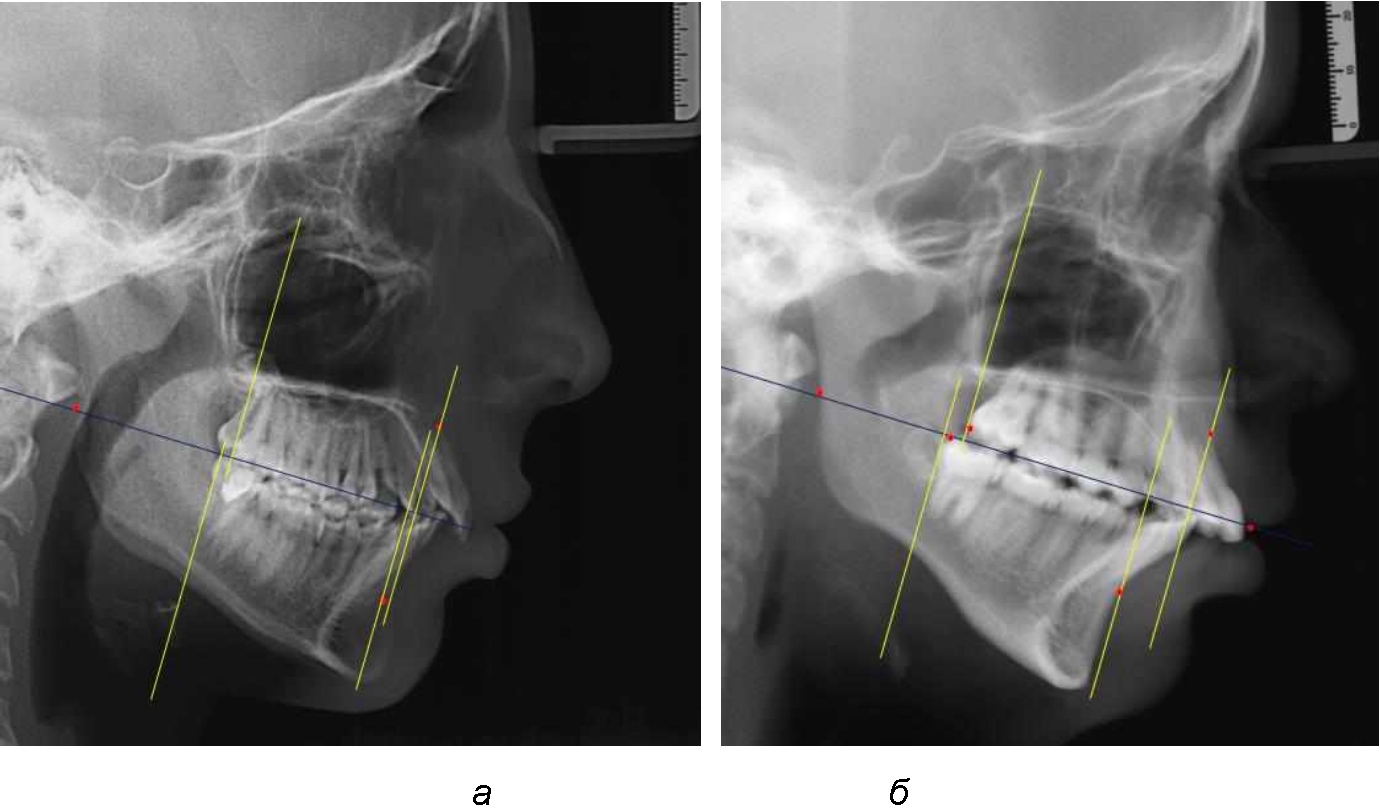

При сагиттальной патологии прикуса встречались варианты, при которых отмечалось равенство либо не равенство альвеолярно-ден-тальных размеров челюстей. Однако вне зависимости от этого, как правило, была отмечена разница в положении челюстей, измеряемая от конструируемой точки «rmРOcP» до точек апикальных базисов по Downs. С дистальной окклюзией было 20 снимков и с мезиальной окклюзией – 19 снимков.

Характерной особенностью мезиальной окклюзии было увеличение расстояния между проекционными апикальными точками, при котором существенно смещалась кпереди нижняя челюсть, а Wits-число имело отрицательные значения. Также дистальная точка нижнего моляра была расположена кпереди от верхней дистальной точки окклюзии второго моляра. Относительно равными считались показатели альвеолярно-дентальных размеров, при которых разница не превышала 1,5 мм. Тем не менее расстояние «rmРOcP-B(SM)» превышало расстояние «rmРOcP-A(SS)» в среднем по группе на (6,87 ± 1,62) мм, что свидетельствовало об аномалии положения челюстей, при котором визуально нижняя челюсть располагалась впереди верхней челюсти (рис. 3).

Рис. 3. Положение апикальных точек и челюстей при мезиальной окклюзии с равными (а) и разными (б) альвеолярно-дентальными размерами зубо-челюстных дуг

В тех случаях, когда при мезиальной окклюзии альвеолярно-дентальные размеры были различными, размер нижней челюсти превышал аналогичный параметр верхней челюсти в среднем на (3,74 ± 1,28) мм.

На рентенограммах с признаками дистальной окклюзии Wits-число имело положительные значения. Дистальная точка нижнего моляра была расположена позади верхней дистальной точки окклюзии второго моляра. Относительно равными, так же как и при анализе снимков с мезиальной окклюзией, считались показатели альвеолярно-дентальных размеров, при которых разница не превышала 1,5 мм. Тем не менее расстояние «rmРOcP-A(SS)» превышало расстояние «rmРOcP-B(SM)» в среднем по группе на (5,29 ± 1,47) мм (рис. 4).

Рис. 4. Положение апикальных точек и челюстей при дистальной окклюзии с равными (а) и разными (б) альвеолярно-дентальными размерами зубочелюстных дуг

В тех случаях, когда при дистальной окклюзии альвеолярно-дентальные размеры были различными, размер нижней челюсти превышал аналогичный параметр верхней челюсти, в среднем на (3,62 ± 1,12) мм.